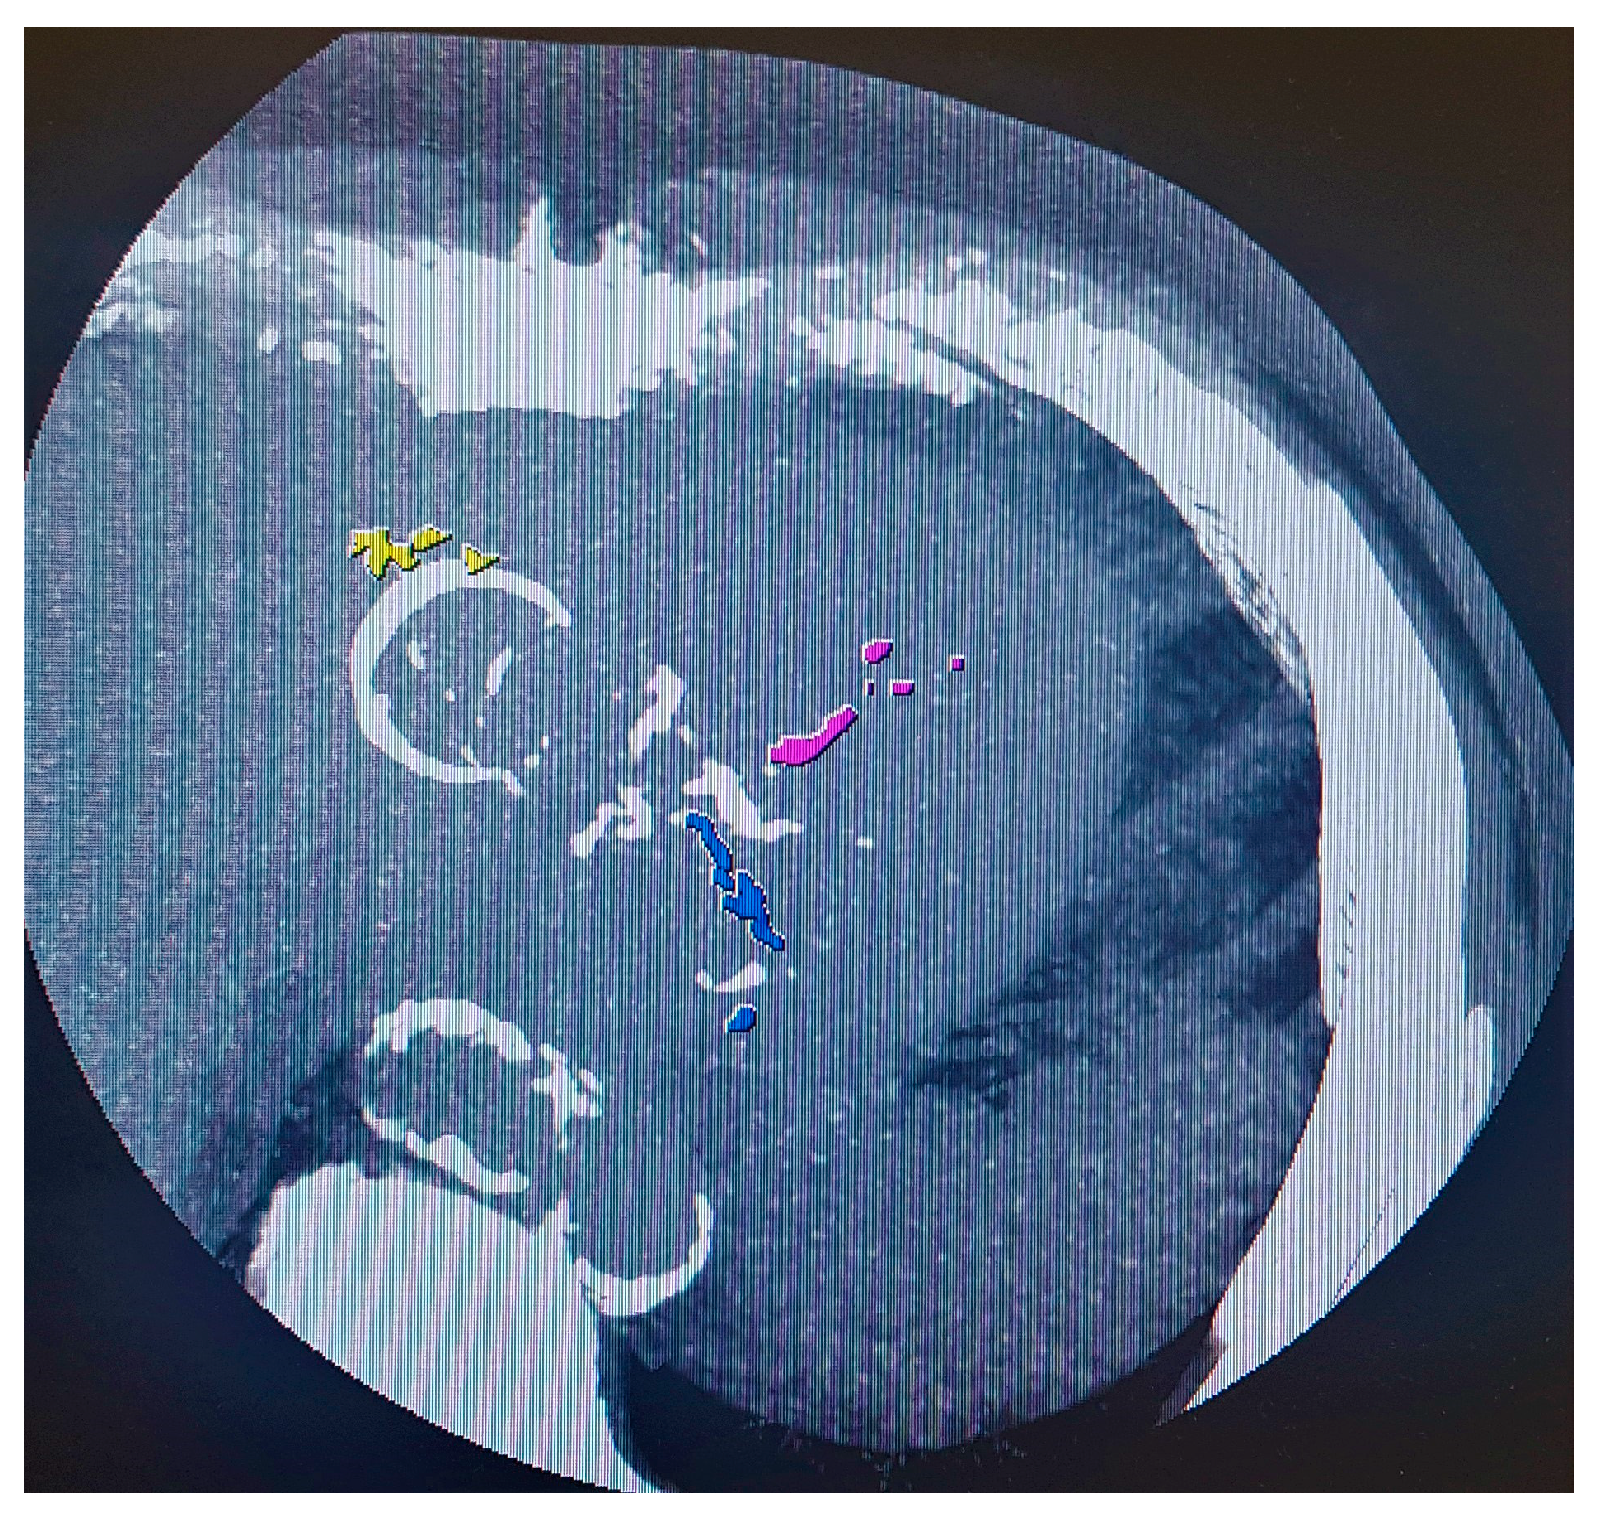

6. 18F-Fluorodeoxyglucose Positron Emission Tomography (FDG PET)